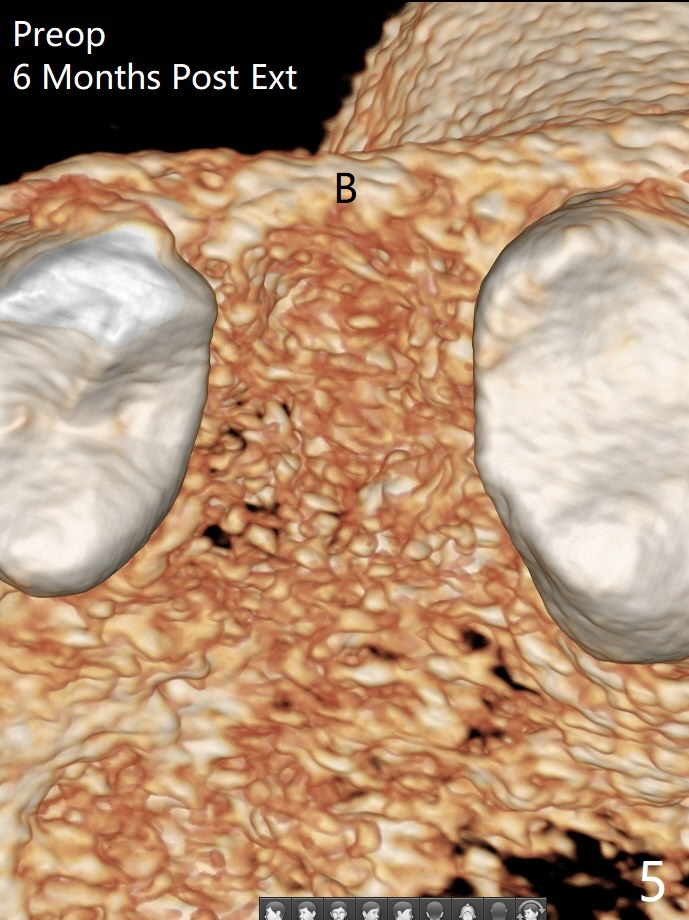

When a 4x11 mm FC is placed to the depth at #13, the palatal crestal bone is indistinct on probing. The implant is then placed ~ 1 mm deeper. To avoid contact between the future abutments and the mesiobucco-distal crest, a 5.5 mm profile drill is used. It appears that a 5x4 mm healing abutment has clearance from the crest (Fig.1,2 C). Immediate postop CT 3 D palatal view shows slight possible implant (Fig.3 I) thread exposure disto-palatal. To avoid this situation, the implant should have been designed more buccal (Fig.4 coronal section) because of the preexisting palatal defect (Fig.5,6) with low bone density palatocoronally (Fig.7). CT should have been taken prior to extraction. PRF or GEM21S should have been used. The patient will return for restoration (probably progressive loading) 3 months postop. In fact a pair abutment is placed 6 months postop (due to coronavirus, Fig.8). There is crestal bone palatal to the implant 6.5 months postop (Fig.9).